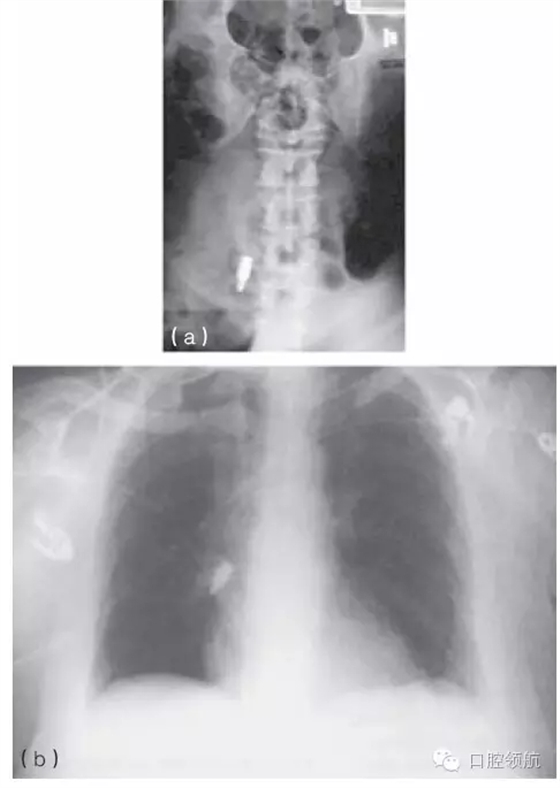

一旦器械或是其他異物,如種植體部件不慎誤吞,應(yīng)立即讓患者拍攝胸片進(jìn)行評(píng)估(圖10.42a,b)。應(yīng)咨詢(xún)專(zhuān)家是否應(yīng)將異物取出,或是通過(guò)胃腸道排出。

圖10.42 (a,b)X線片顯示被誤吞的螺絲刀。